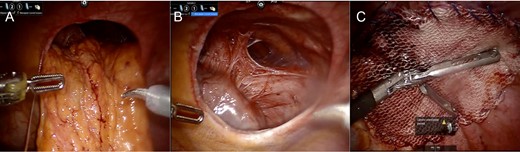

Imaging from Case #2. (A and B) Preoperative CT scan demonstrating loop of bowel in the thoracic cavity posterior to the heart and LVAD. (C) Postoperative CT scan, coronal view demonstrating repair of the diaphragmatic defect with mesh overlay.

A 43-year-old male with a past medical history significant for non-ischemic cardiomyopathy (NICM) treated with a Heartmate II LVAD and a biventricular implantable cardioverter defibrillator presented to the emergency department with new-onset change in vision, weakness of hands and numbness of upper extremities. The patient was admitted for a TIA evaluation. Due to complaints of daily vomiting a barium swallow was ordered, which demonstrated mesenteroaxial gastric volvulus. A subsequent CT scan demonstrated a diaphragmatic hernia (Fig. 3A and B) and the patient was brought to the operating room for robotic repair of the diaphragmatic hernia.

A diaphragmatic hernia was noted immediately adjacent to the LVAD. The herniated intestinal contents were reduced without signs of visceral ischemia. A 20-cm round Parietex mesh was used to bridge the hernia defect, incorporating the LVAD device. The mesh was secured to the diaphragm using running 0-prolene suture. Postoperative course was uneventful and the patient was discharged following therapeutic anticoagulation. Postoperative imaging revealed repaired diaphragmatic defect without evidence of recurrence (Fig. 3C).